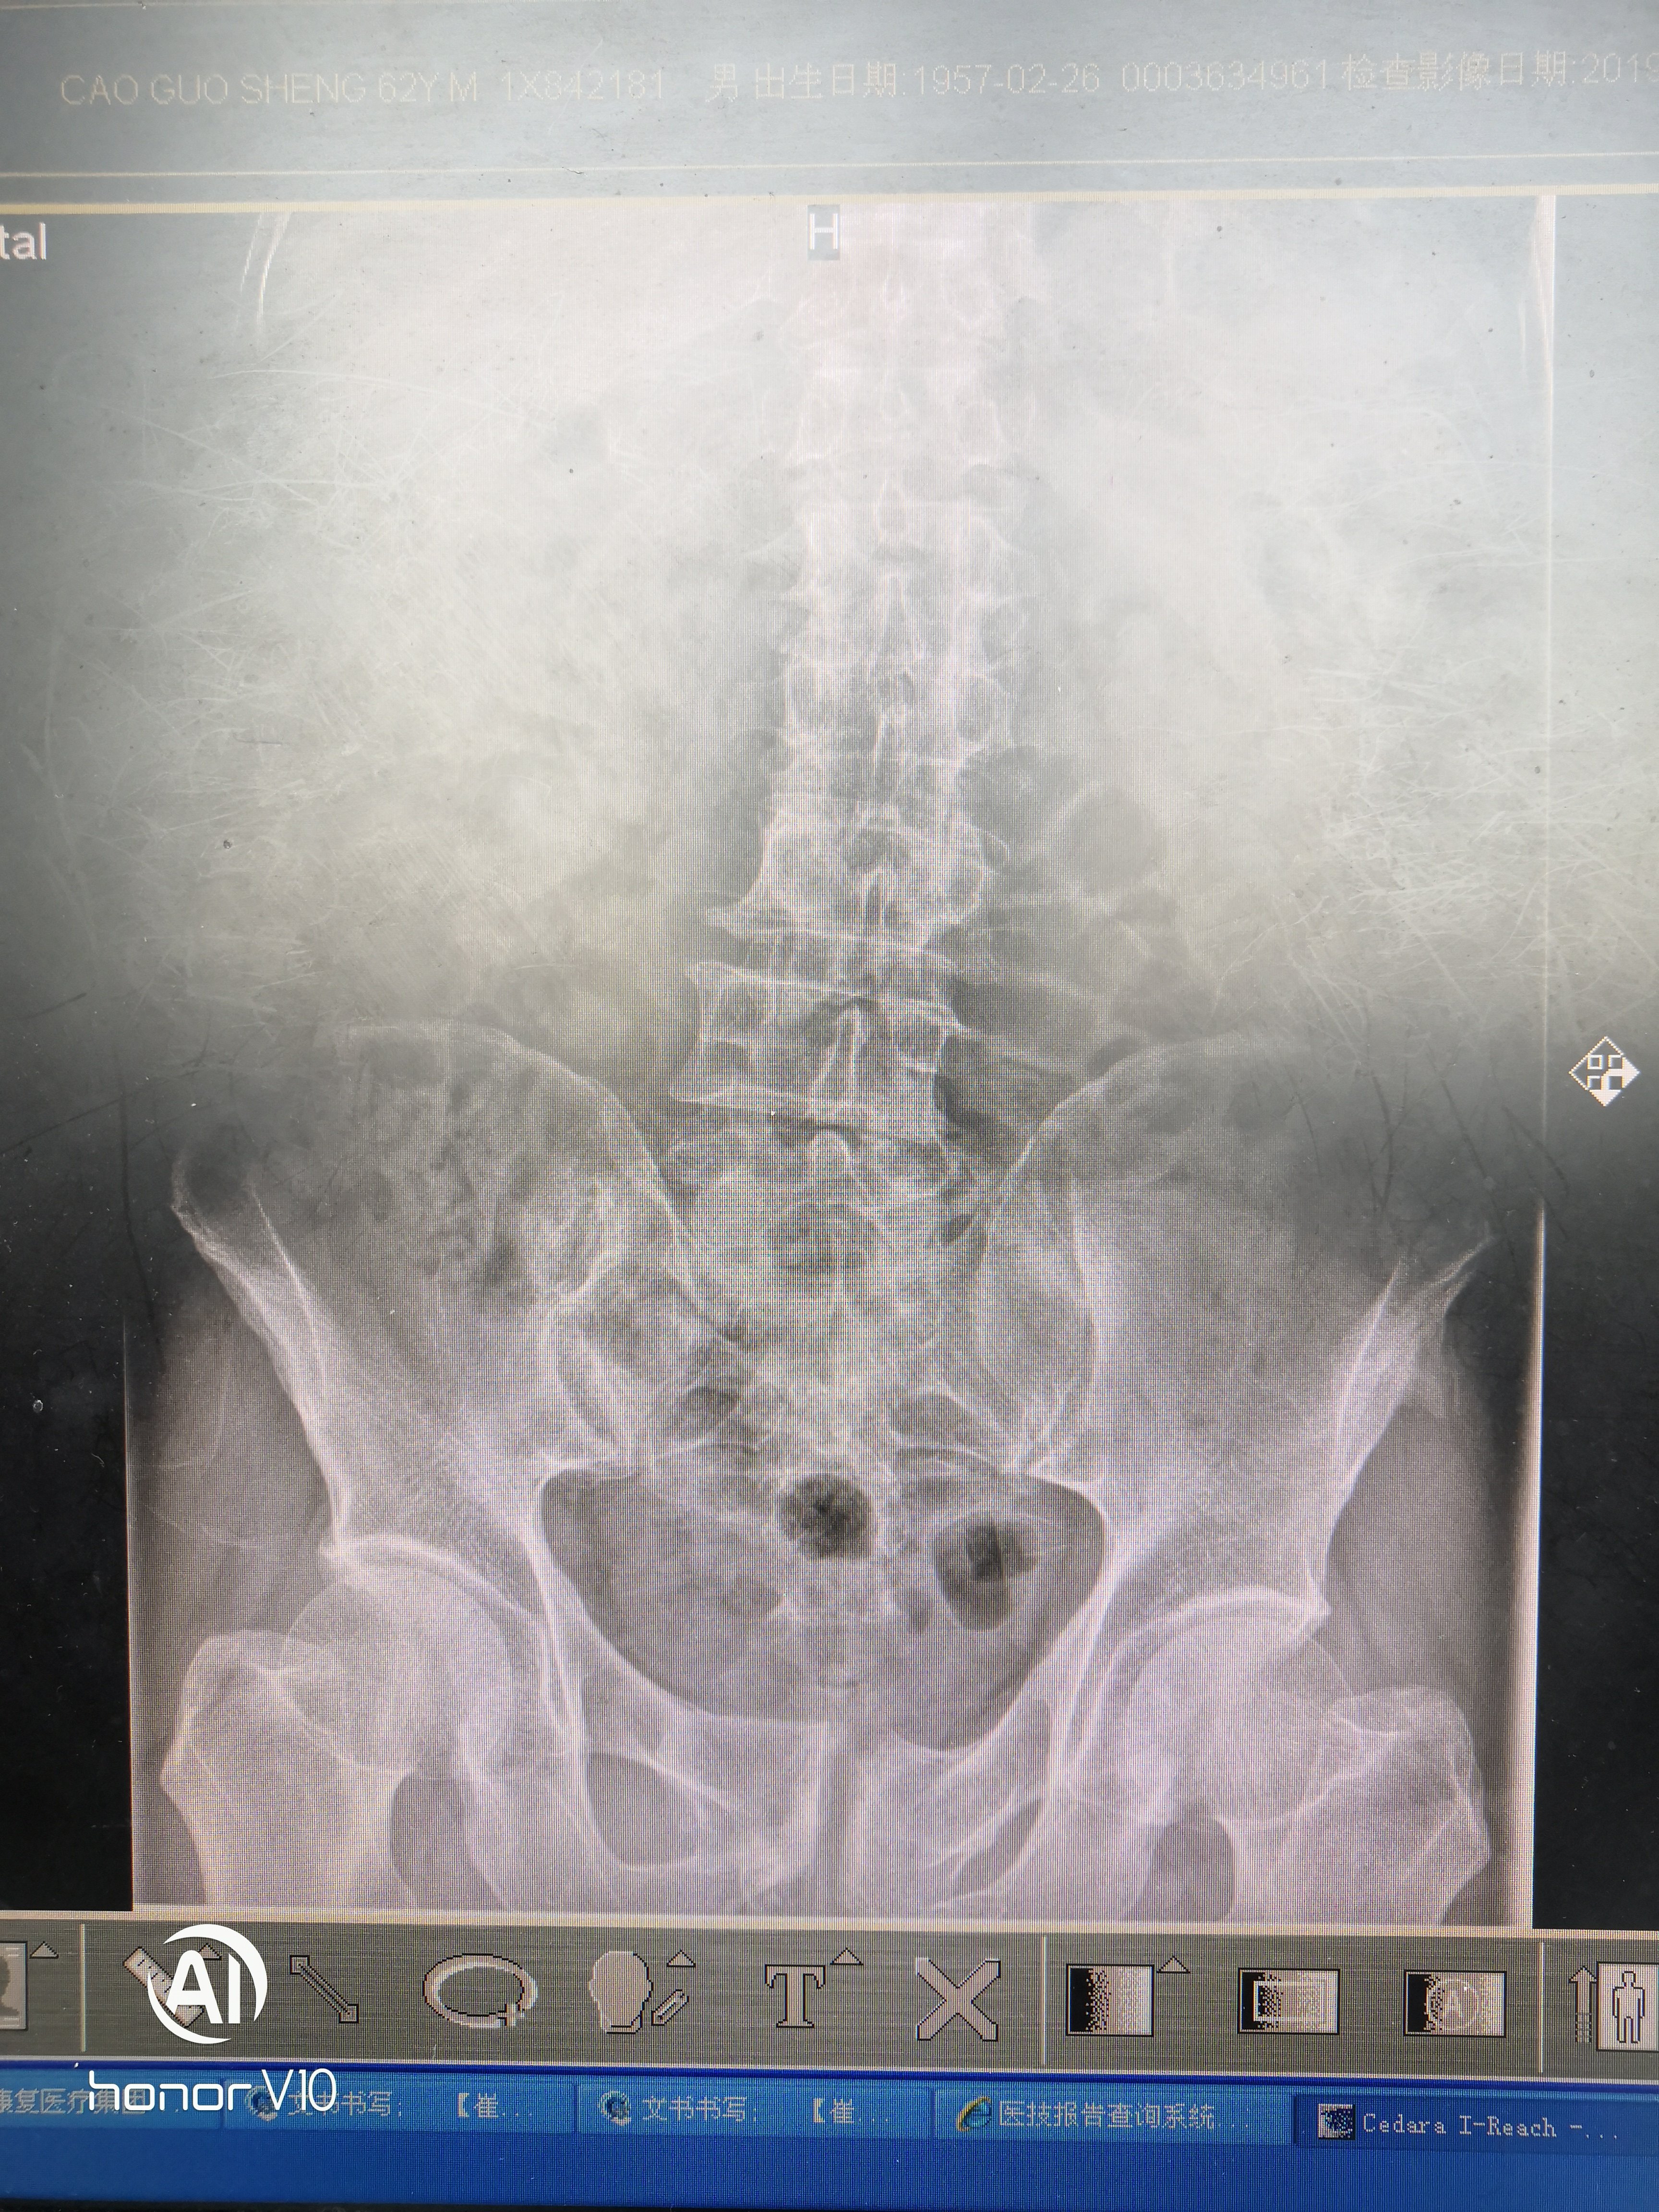

图 膀胱结石x光片

膀胱结石求诊

在拍摄脊柱部位的x光时,医生意外发现李先生膀胱和左肾竟然各有一个

【原创】膀胱结石(超大)不看会后悔哦.

膀胱结石